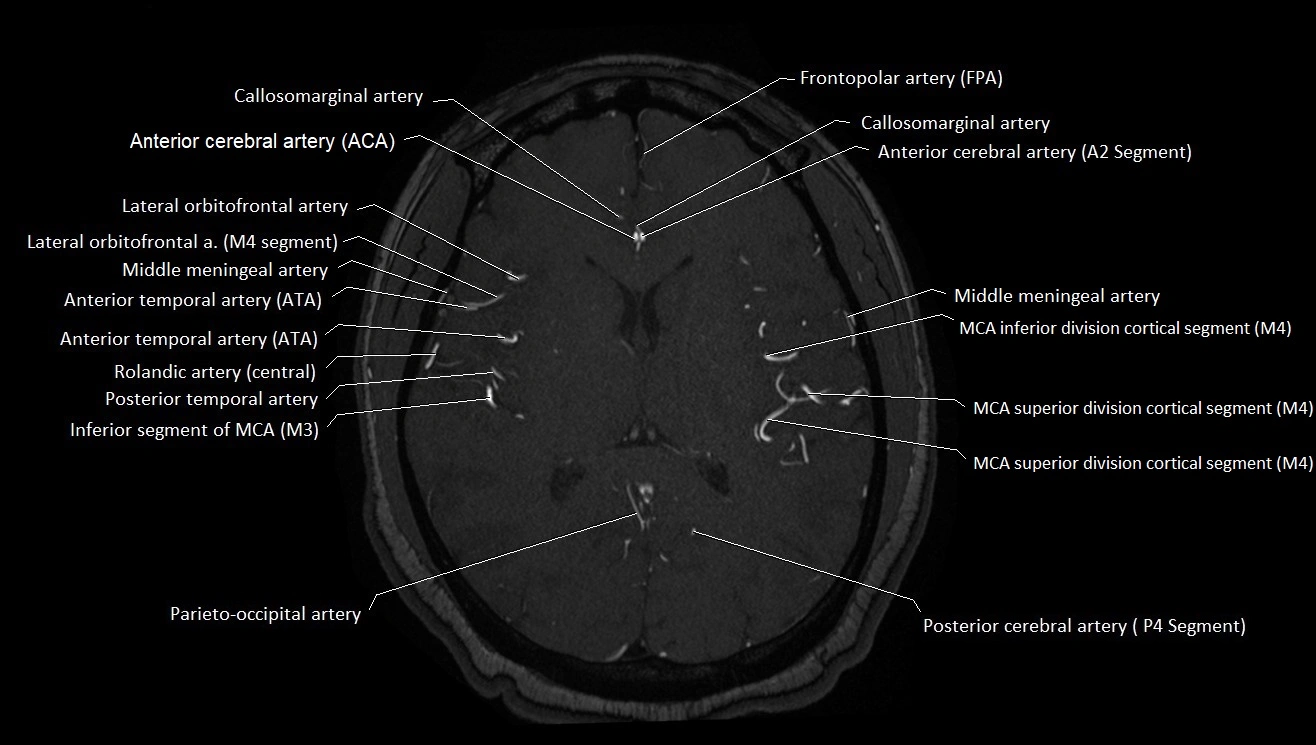

MRI Appearance

T1-weighted images:

• Vessel appears as a flow void (dark lumen) near the optic tract and temporal horn

• Surrounding parenchyma intermediate signal

T2-weighted images:

• Vessel lumen shows dark flow void

• Ischemic infarcts in its territory (internal capsule, thalamus) appear hyperintense

MRA (Magnetic Resonance Angiography):

• Flow-related enhancement makes the AChA appear as a bright, linear vascular signal against suppressed background

• High sensitivity for origin and proximal course; distal branches may be too small to resolve

• Detects stenosis, occlusion, aneurysm, AVM feeders